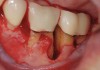

The workshop's group on periodontal soft-tissue root coverage procedures evaluated the predictability of root coverage procedures for single- and multiple-tooth Miller Class I and II10 periodontal recession defects. The workshop concluded that predictable root coverage was possible for Miller Class I and II recession involving a single tooth. When compared with the use of acellular dermal matrix graft (ADMG) (donor tissue) or EMD (porcine origin), procedures using a subepithelial connective tissue graft (SCTG) harvested from the patient's palate provided the best root coverage outcomes in conjunction with a coronally advanced flap.11 As alternatives to autogenous donor tissue, the workshop found strong evidence to support the use of an ADMG or EMD in conjunction with a coronally advanced flap and limited evidence to support the use of platelet-derived growth factor and xenogeneic collagen matrix.11 In addition, root coverage procedures were found to be effective for Miller Class I and II recession defects affecting multiple teeth, although the evidence is limited.11 Figure 1 and Figure 2 show the pretreatment and 1-year postoperative views of a soft-tissue root coverage treatment with SCTG and EMD that used a coronally advanced flap and a tunneling procedure. Figure 3 and Figure 4 depict the pretreatment and 3-year postoperative views of a root coverage procedure with ADMG and EMD that used a coronally advanced flap and a tunneling procedure (this patient was noncompliant following surgery and did not return to the office until the 3-year postoperative appointment).

(1.) Pretreatment view of single incisor with gingival recession exposing the root.

Figure 1